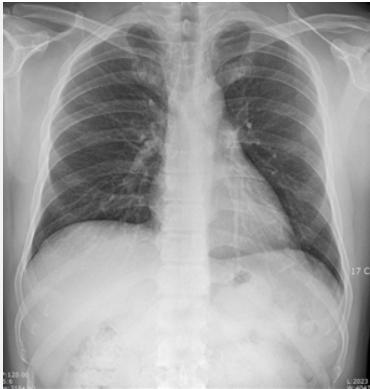

네 아직 남아있습니다. 정상 엑스레이는 아래와 같아요.